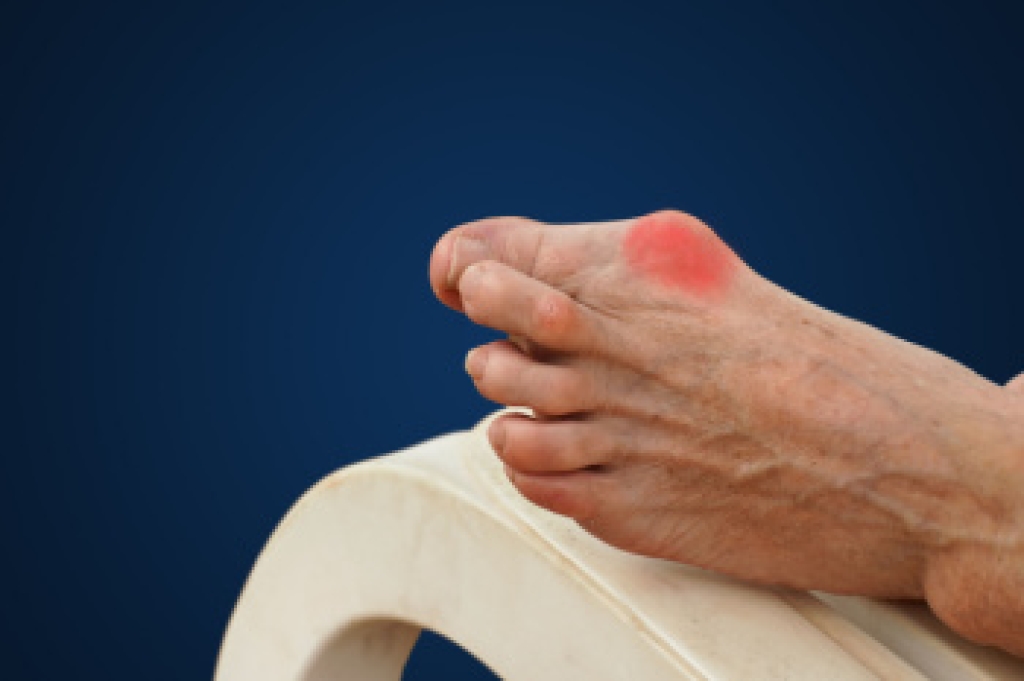

There are a multitude of foot and ankle conditions that can impact your daily life. Conditions like plantar fasciitis, which causes sharp heel pain, occur when the tissue connecting the heel to the toes becomes inflamed. A bunion, a bony protrusion at the base of the big toe, can cause swelling and discomfort. Corns, which are thickened areas of skin, typically develop on toes due to friction and can be painful. Issues with toenails, such as ingrown toenails or fungal infections, can lead to redness, swelling, and discomfort. While some minor problems may improve on their own, persistent pain, swelling, or changes in the nails warrant professional evaluation. Ignoring these issues can lead to further complications, so it is important to seek medical advice. If you are experiencing any of these symptoms, it is suggested you schedule an appointment with a podiatrist for an accurate diagnosis and personalized treatment plan.

- Bunions